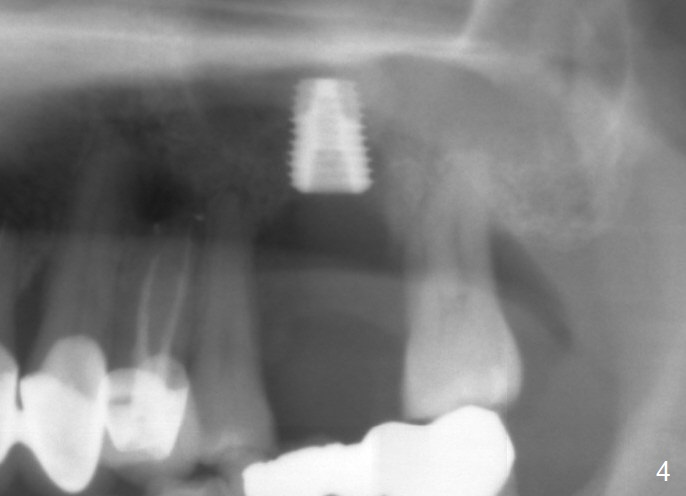

When the tooth #14 is extracted, the buccal plate is lost, while the apex of the palatal socket is perforated.  The palatal slope of the septum appears to be a suitable site for osteotomy, but the depth seems to be 2 mm.  After sequential osteotomy until 5.3 mm with drills, a 5.9 mm SM tap obtains stability (Fig.2).  A 5.9x8 mmm implant is placed with barely sufficient stability after 1 piece of PRF membrane and VeraGraft (Fig.2-4).  The implant rotates and dislodges when an abutment is being placed.  Neither do 6-8x17 mm Tatum taps achieve primary stability.  Socket preservation is performed, followed by periodontal dressing (Fig.5).  Primary stability might have been obtained if a smaller IBS implant with fins were placed in the palatal socket.  The periodontal dressing has dislodged 1 week postop; the socket appears healing (Fig.6,7).  Bone graft seems to be minimal or bone density of the graft is low (Fig.8).  The socket heals with a wide ridge 2 months post socket preservation, but the tooth #15 seems to be buccal (Fig.9) and mesial (Fig.10) shift.  After use of Magic Split and Expanders (until 3.8 mm for 13 mm), try 5 mm dummy implant (Fig.11).  If 6 mm one fails to achieve stability substantially, switch to 7 mm Tatum tapered tap provided there is enough mesiodistal space (use 8 mm implant positioner to gauze the space beforehand (preop)).  Consider using Vanilla (not Vera) Graft to fill in the gap between implant and osteotomy.  When primary stability is obtained, place a nonfunctional provisional to prevent further shifting (Fig.11 white outline).  After osteointegration, use the provisional (reline and separator) to distalize the tooth #15.